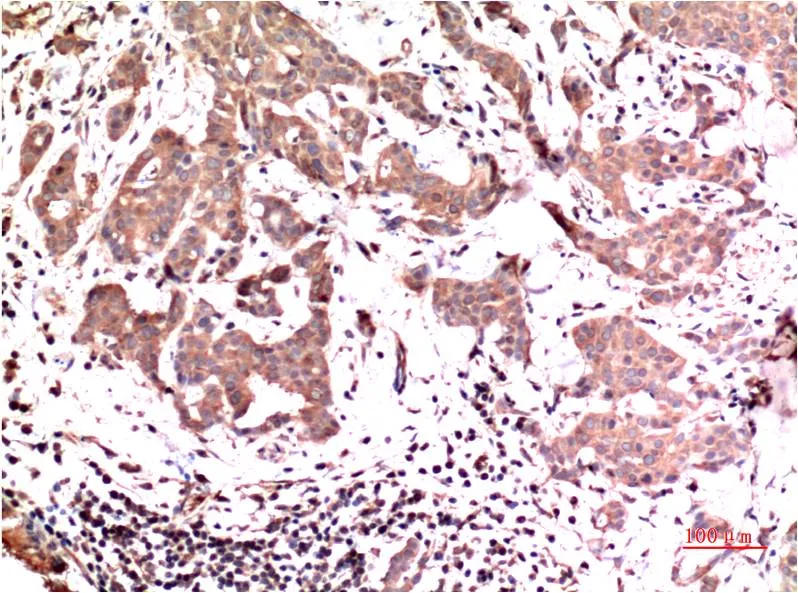

JAK1 (8D8) Mouse Monoclonal Antibody

Cat: AMM00786

Application:IHC-P

Reactivity:Human,Rat,Mouse

Conjugate:Unconjugated

Gene Name:JAK1